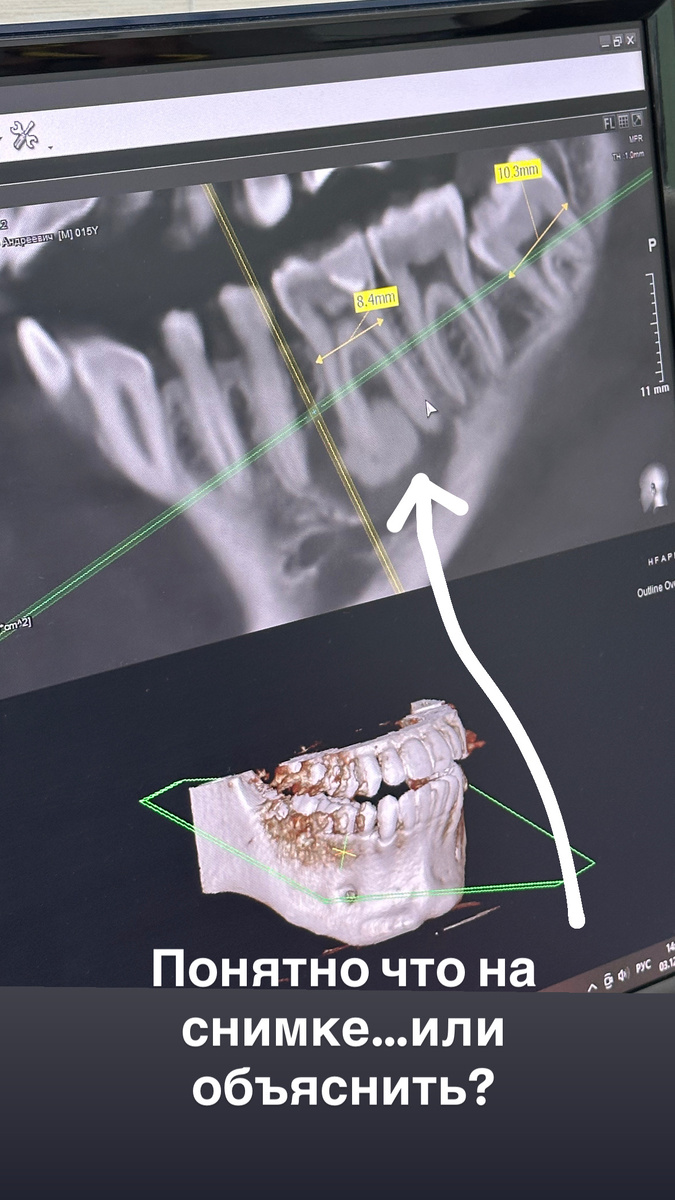

Исходная ситуация на компьютерной томограмме.Сейчас все поймете. Мы пересадили зуб вместо импланта: уникальная операция для Тамбова Недавно в нашей клинике произошёл случай, о котором стоит рассказать отдельно.

Исходная ситуация на компьютерной томограмме.Сейчас все поймете.

Мы начали с КТ.

На основании данных:

• оценили расположение опухоли,

• расстояние до нижнечелюстного канала,

• анатомию лунки удаляемого зуба,

• форму и размеры зуба мудрости.